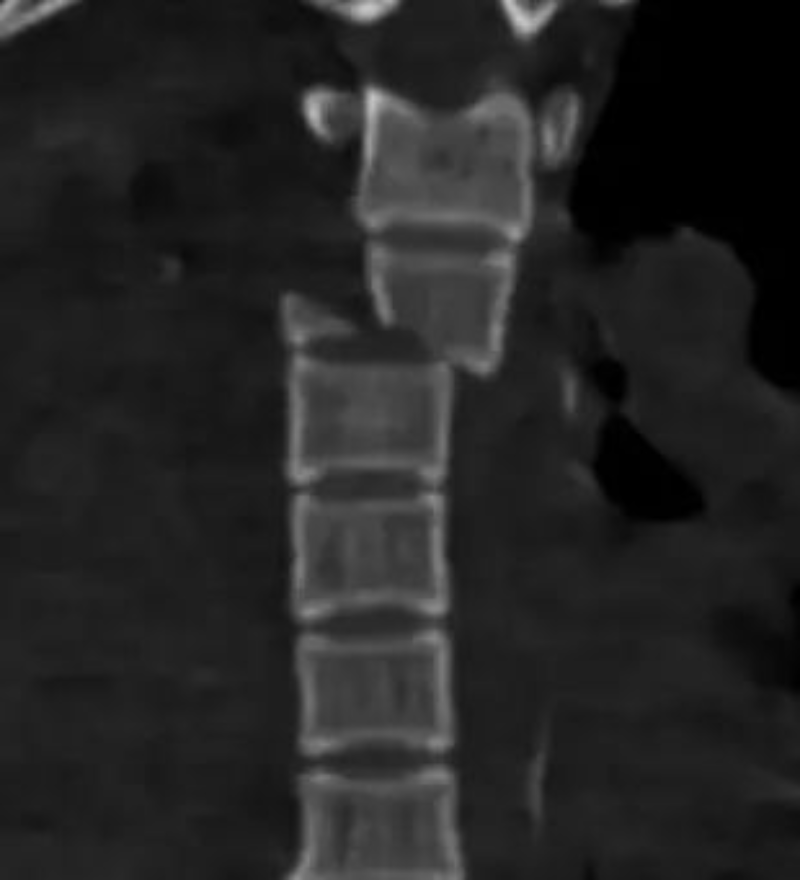

胸4椎體爆裂性骨折伴脫位

胸12椎體爆裂性骨折,骨折碎塊壓迫椎管